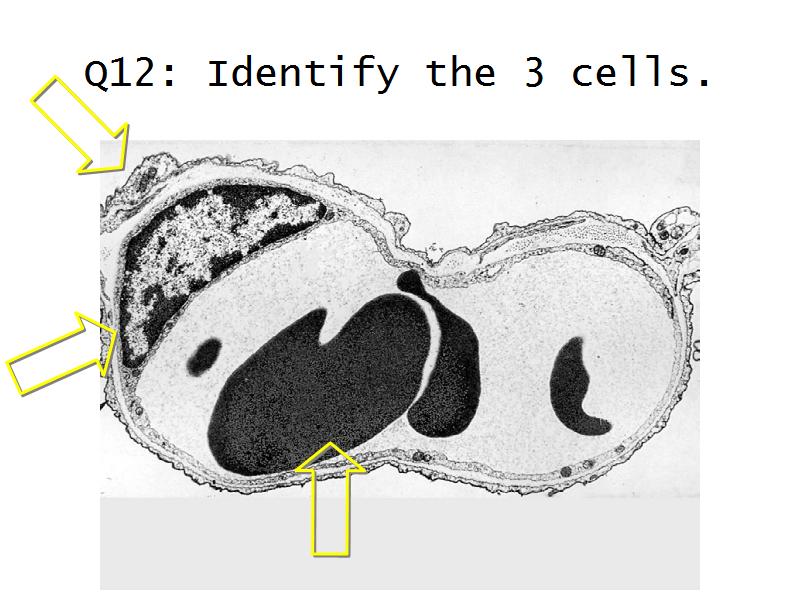

Kidney

Slides 28 & 76

Kidney: Objectives

- Basic arrangement of nephrons and collecting tubules in the kidney

- Structure of the nephron and collecting tubules

- The renal corpuscle

- Make an annotated diagram of a nephron, including the juxtaglomerular apparatus. Indicate the flow of blood and water in each part, and how solutes are filtered, secreted and reabsorbed.